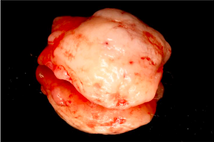

- Non-surgical periodontal therapy was performed to reduce gingival inflammation and swelling

- Surgical removal of excessive gum tissues and extraction of multiple poor prognosis teeth were carried out as well

- She was kept under strict follow up and advised to comply with meticulous oral hygiene measures throughout treatment